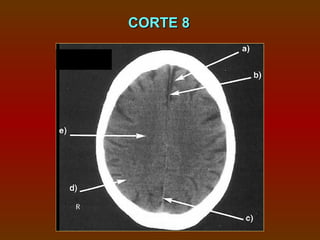

CORTE 8

a) Fissura inter-hemisférica

b) Foice anterior do cérebro

c) Foice posterior do cérebro

d) Substância cinzenta

e) Substância branca